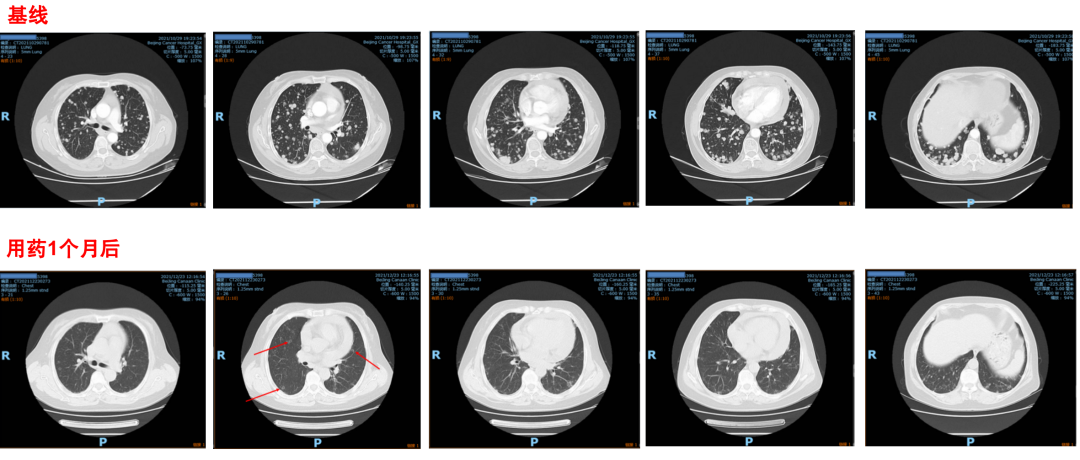

患者丁**,女,61岁 主诉: 咳嗽1月。 ?? 2021年10月 胸部CT提示:双肺多发结节,考虑转移。纵隔、双锁骨上区多发肿大淋巴结,考虑转移。心包积液。 ?? CT引导下右肺下叶占位穿刺活检,病理提示:肺腺癌,伴实性和微乳头结构;免疫组化结果:ALK-Ventana(+)【对照ALK-Nega(-),ALK-Pos(+)】,C-met(强阳80%+),HER2(1+)【HER2阳性对照(+),HER2阴性对照(-)】,Ki67(10%+),pan-TRK(-),PD-L1(22C3)(TPS=15%)【PD-L1(22C3)阳性对照(+),PD-L1(22C3)阴性对照(-)】,ROS-1(-),TTF1(+),NapsinA(+),WT-1(-)。 完善分期检查 ?? 2021-10-29我院PET-CT提示:①双肺弥漫多发结节,代谢活跃;②双锁骨区、纵隔多发淋巴结肿大,代谢活跃;以上倾向恶性,建议进一步检查明确病理除外肉芽肿性病变。③心包积液。 ?? 头部MRI未见明显转移征象。 ?? 临床诊断为:右肺腺癌IV期( T4N3M1) 双肺多发转移、双侧锁骨上及纵隔淋巴结转移、心包积液,ALK-Ventana(+) ,C-met(强阳80%+) EML4—ALK融合的发现及致癌机制 □ 2007年日本科学家首次在肺腺癌肿瘤组织中发现EML4-ALK融合1 □ ALK是强力致癌驱动基因,驱动机制主要分为基因融合、基因扩增、基因点突变,其中EML4-ALK融合最为常见,ALK融合蛋白可以激活关键致癌信号通路,导致肿瘤细胞恶行增值2,3 □ ALK+NSCLC发生率为3%~7%,中国人群腺癌ALK阳性率为5.1%4,5 ALK抑制剂发展之路 NCCN指南:ALK阳性NSCLC一线治疗方案概述 病史: □ 二代ALK-TKI较一代ALK-TKI具有显著的获益优势 □ 二代ALK-TKI(BIRC评估): 递增期 150-250mg 各剂量组均观察到肿瘤响应 □ 剂量递增期 150 mg、200 mg、225mg 和 250 mg 各剂量组 ORR 分别为 33.3%、87.5%、100%和 100% □ DCR 分别为 66.7%、100%、100%和 100% 疗效评价 ? 2021-11-19开始口服恩沙替尼 225mg QD治疗。 ?1个月后(2021-12-23)复查评效PR(大部分病灶消失)。 安全性 ? 皮疹3级 ? 肝功能异常2级(ALT/AST升高) ? 发热1级(间断体温升高) 不良反应及处理 ? 皮疹:局部外用含激素的软膏 ? 肝功能异常:给予口服保肝药物治疗后肝功能异常恢复至1级 ? 发热:物理降温 ? 综合考虑患者的耐受性,恩沙替尼减量至200mg Qd继续治疗 ? 定期复查评效 复查和随访 ? 疗效评价:2022-3-25复查评效近CR(肿瘤几乎消失),PFS:4个月 ? 安全性: 皮肤感觉异常,痛觉过敏 味觉异常 患者自觉耐受性差,2022年4月恩沙替尼减量至175mg QD 治疗和随访 春寒赐浴华清池,温泉水滑洗凝脂 — 白居易《长恨歌》 诊疗过程 恩沙替尼 一线 exalt3数据更新 ? 数据截止到2020年12月8日,中位随访时间27.6个月,在ITT人群中IRC评估的mPFS为31.3个月,在mITT人群中INV评估的mPFS达到33.2个月,IRC评估的mPFS未达到; ? 皮疹和其他皮肤相关毒性(例如瘙痒)发生率最高,其次为分级较低且无临床症状的转氨酶上升和水肿。三级皮疹发生率为11.2%,通过减量等措施可缓解。 总结 该患者一线使用恩沙替尼两次减量,服药四个月后病灶几乎消失,疗效显著,确证了恩沙替尼在ALK阳性晚期NSCLC一线治疗的疗效,减量后恩沙替尼仍可以持续缩瘤。 恩沙替尼一线eXalt3研究已全文发表于全球顶尖学术期刊JAMA Oncology(影响因子为31.777)。截至2020年12月8日的随访数据表明,在ITT人群中,恩沙替尼组BIRC评估的中位PFS达到31.3个月,mITT人群中,恩沙替尼INV评估的中位PFS达到33.2个月,BIRC评估的中位PFS尚未达到。